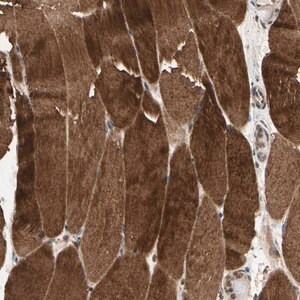

Anti-MAP3K10 antibody produced in rabbit

Prestige Antibodies® Powered by Atlas Antibodies, affinity isolated antibody, buffered aqueous glycerol solution

immunofluorescence: 0.25-2 μg/mL

immunohistochemistry: 1:200-1:500

Mitogen-activated protein kinase kinase kinase 10 recombinant protein epitope signature tag (PrEST)